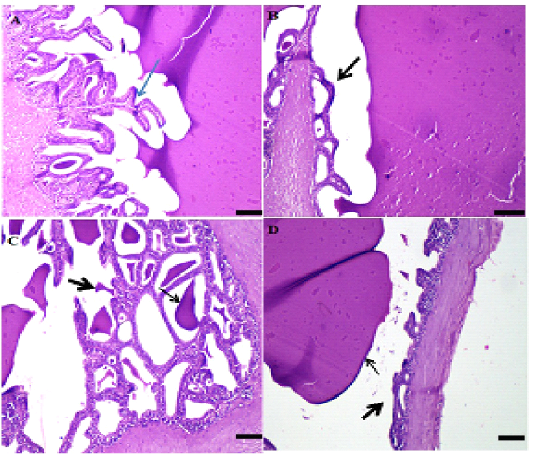

A: Photo micro graph of male rats (control) showing normal seminiferous tubules and active spermatogenesis, seminiferous tubules, interstitium and covering were within normal morphological picture (H&E; x100). B: Photo micro graph of male rat testis showing necrotic seminiferous tubules containing edema and necrotic debris (arrow) and interstitial edema (arrowhead), some seminiferous tubules were necrotic and contained edema and necrotic debris beside interstitial edema, A few tubules had pyknotic spermatogonia and spermatocytes with intense congestion and edema in the interstitium (H&E; x100). C: Photo micro graph of male rat showing intense edema and necrosis of the seminiferous tubules and arrest of spermatogenesis (arrows), the majority of tubules showed arrest of spermatogenesis with intense necrosis and edema inside their lumina severe edema and congested blood vessels in capsule and interstitium (H&E; x100). D: Photo micro graph of male rat testis showing spindle cell invasion for necrotic seminiferous tubules (arrows) and interstitial edema, the majority of necrotic acini invaded by spindle cells with mononuclear cells infiltration beside interstitial edema , other tubules collapsed with loss of thus lining epithelium and contained necrotic debris and threads. Dilated blood vessels with prominent edema in interstitium (arrow) (H&E; x100).